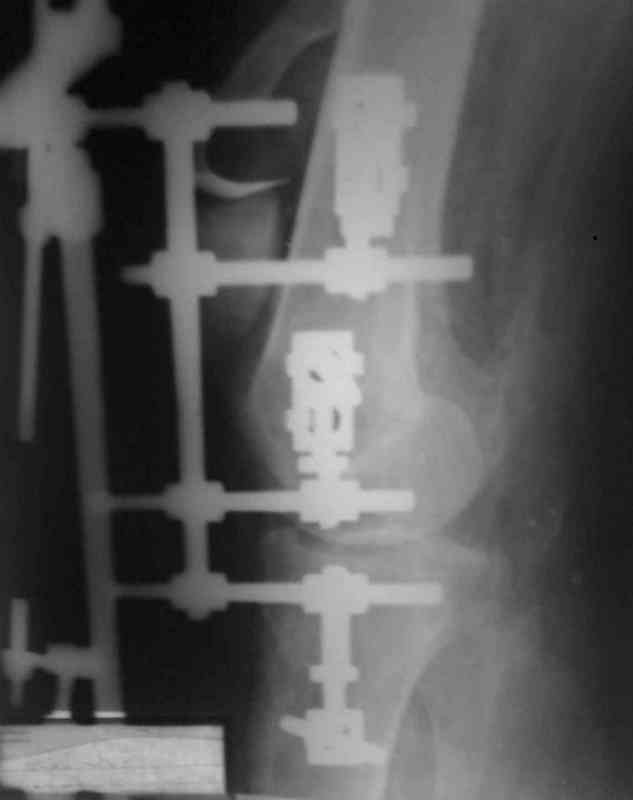

При пользовании стержневых наружных фиксаторов,

надо придерживаться правила проведения стержней подальше от зоны, на бедре лучше накладывать стержни косо передне-латерально, между брюшками прямой и vastus lateralis, а на голени по передне-медиальной поверхности большеберцовой кости, где отсутствует мышцы, иначе

восстановление движения в суставе тяжелее из-за

прошитых мышц спицами или стержнями аппарата.

Снимки прошлых публикации из моего Power point